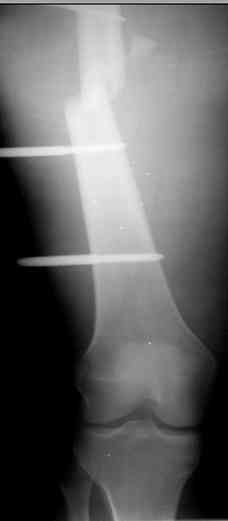

Коллеги! Прошу совета, какую тактику избрать при лечении.Больной 27 лет, мотоциклист. Поступил 23.04.10 ДЗ. О. перелом н.з левого бедра Gustillo 3b (c повреждение бедренной вены), О.Правого бедра Gustillo 2, з. фрагментарный перелом левой голени.При поступлении Hb 66 ISS 40, Фиксация стержневыми аппратами, сосудистые хирурги выполнили шов вены. Выполена резекция бедренной кости 9 см. На 7 сутки Желудочно-кмшечное кроветечение из стрессовых язв, 12 сутки флотирующий тромтоз 14 см установлен кава-фильтр. На 15 сутки закрытие ран местными тканями. Раны заживают первично. Воспаления на стержнях нет. В настоящий момент планируем. Переход со стержневых аппаратов на стержни с антибактериальным покрытием на правом бедре и левой голени. Левое бедро планируем продолжить фиксировать в стержневом аппарате.

Вопрос: что делать с левым бедром? Учитывая внутрисутавной характер перелома, дефект бедра 9 см.

На левом бедре оставили аппарат бедро-голень.

Как вы думаете если сделать следующее.

После заживления раны на левом бедре. Выполнить открытую реподицию и синтез пластиной для дистального бедра. Пластину в проксимальном направлении зафиксировать монокортикально.

А затем выпонить остеотомию бедра в верхней трети.

И тракцию бедра на стержне. Типа (СМ картинки).

После выращивания регенерата стержень блокировать.